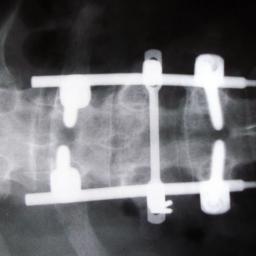

Telstra cloudwhacks storage vendors' sweet spot

Cloudy medical image library is bad news for big storage Australia's dominant telco, Telstra, has waded into one of the storage industry's favourite markets, medical imaging, with a cloud service that may not make it a lot of friends.…